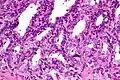

Microanatomía

El revestimiento interno de las vesículas seminales (el epitelio) está formado por un revestimiento de células intercaladas en forma de columna y de cubo.[7] Existen diversas descripciones del revestimiento como pseudoestratificado y formado únicamente por células en forma de columna.[8] Cuando se observan al microscopio, se ve que las células tienen grandes burbujas en su interior. Esto se debe a que su interior, llamado citoplasma, contiene gotitas de lípidos que intervienen en la secreción durante la eyaculación.[7] El tejido de las vesículas seminales está lleno de glándulas, espaciadas irregularmente.[7] Además de glándulas, las vesículas seminales contienen músculo liso y tejido conjuntivo.[7] Este tejido fibroso y muscular rodea las glándulas, ayudando a expulsar su contenido.[3] La superficie externa de las glándulas está cubierta de peritoneo.[3]

Micrografía a bajo aumento de la vesícula seminal. Tinción de H&E.

Micrografía a bajo aumento de la vesícula seminal. Tinción de H&E. -

Micrografía a gran aumento de la vesícula seminal. Tinción H&E.

Micrografía a gran aumento de la vesícula seminal. Tinción H&E.